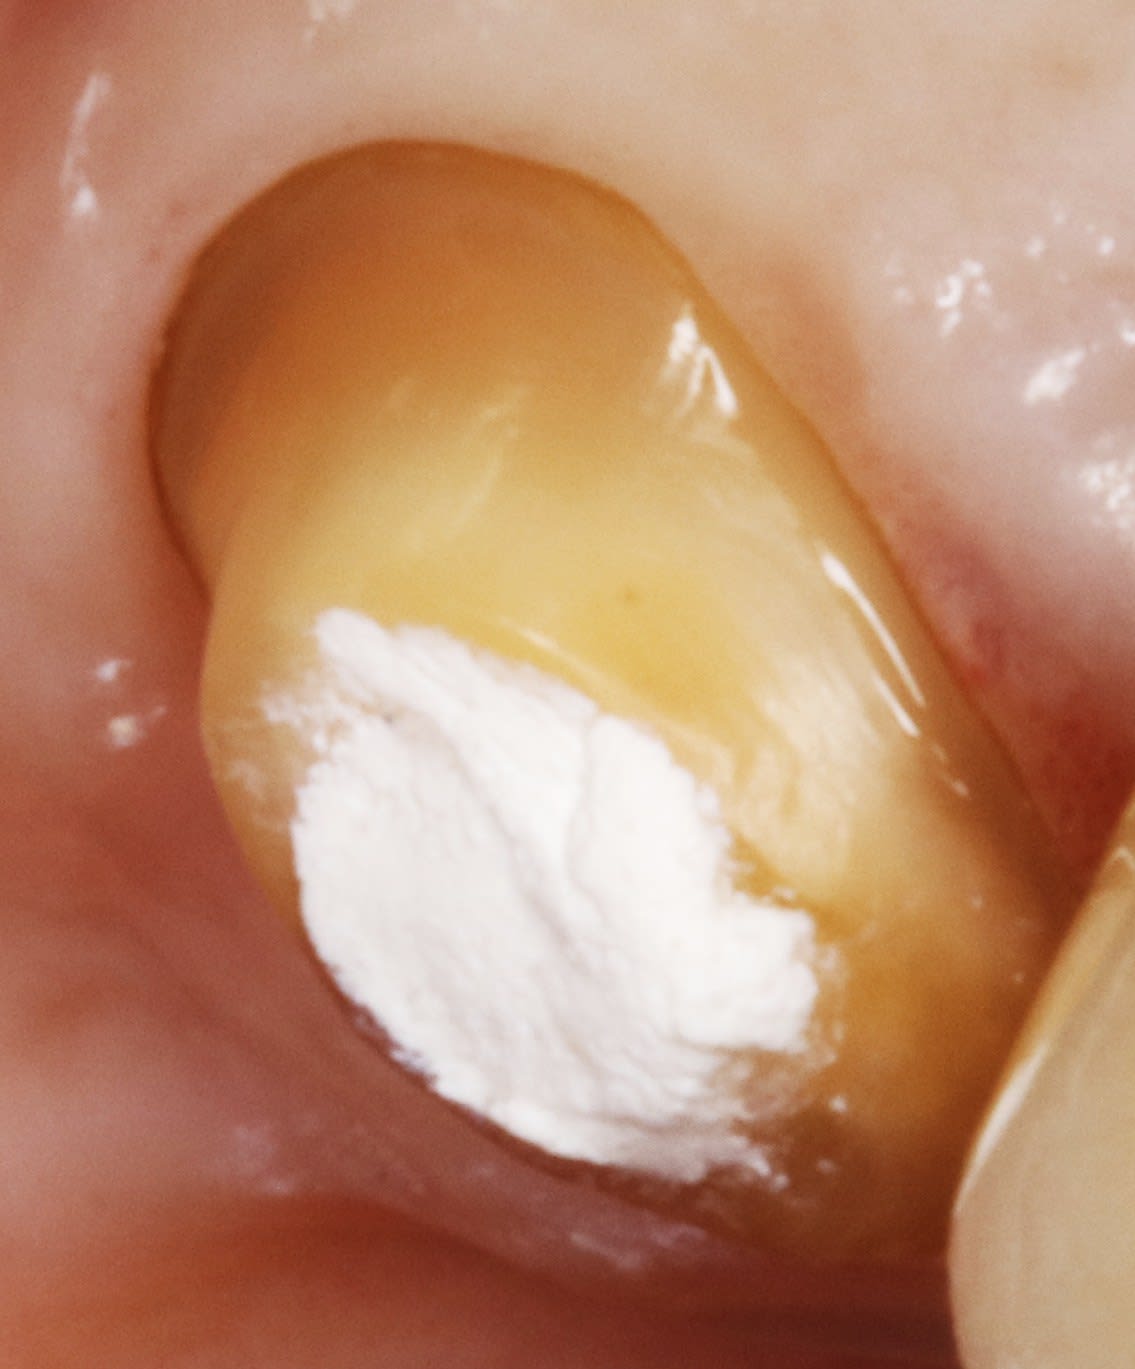

et pour finir , ç est le cas de ma 25 de la page 4 .

on a donc pris l empreinte apres avoir descendu les limites la semaine passée .

aujourd'hui , il est comme ça : la gencive a effectivement recouvert les limites , mais gentiment , tranquille .

et il suffit de sceller la ceram , et hop , on en parle plus .